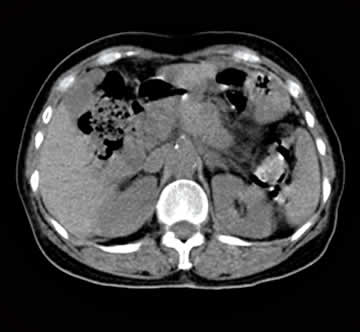

超音波装置を使用して肝臓・膵臓・腎臓等のおなかの中の臓器の状態を見る検査です。腫瘍の有無や臓器の大きさを調べて、病気や肥大などがないかを確認します。また、メタボリック症候群に代表されるような脂肪肝や胆石・腎結石などの診断にも有効です。